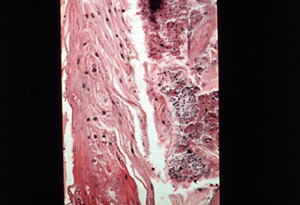

Microscopía de la lengua vellosa |

Esta microfotgrafia ilustra la

situación patológica. Hay marcado alargamiento de las papilas

filiformes con la

acumulación de desechos de alimentos (detritus), necrosis,

células descamadas y microorganismos abundantes entre las

papilas. La falta de frotamiento mecánico normal de la superficie puede

considerarse causa del alargamiento de las papilas filiformes

y acumulación de desechos. |

A mayor resolución de la imagen

anterior se observa necrosis, microorganismos y células

paraqueratinizadas de

una larga papila filiforme. |